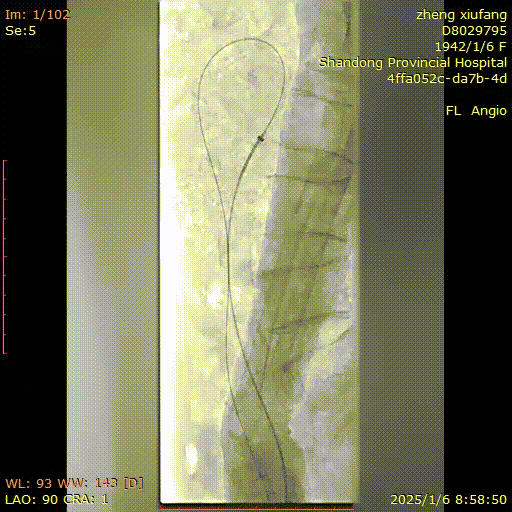

患者取仰卧位,常规消毒铺巾,1%利多卡因局麻后,逆行穿刺右侧股动脉,置入6F血管鞘,泥鳅导丝配合猪尾导管送至胸12水平,正位及侧位造影见肠系膜上动脉起始部钙化严重,可见支架影,支架内重度狭窄,肠系膜上动脉中远段延迟显影。经右股动脉入路更换7F 55cm RDC长鞘,导丝、导管配合选入肠系膜上动脉并通过病变段,建立轨道。沿导丝送入4mm球囊扩张病变段,扩张后造影见肠系膜上动脉支架内狭窄较前有所改善。再沿导丝送入7mm✖60mm震波球囊,扩张后再次造影示:肠系膜上动脉显影较前明显改善,支架内造影剂通过顺利,未见明显残余狭窄,无造影剂外溢,遂决定结束手术,缝合器缝合穿刺点,无菌敷料加压包扎,手术过程顺利,术后患者安返病房。

建立入路

7*60mm震波球囊